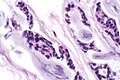

Adenoid cystic carcinoma. H&E stain. | |

| LM | cribriform architecture (other patterns: solid, cords, (bilayered) tubules), cystic spaces filled with basophilic material, scant cytoplasm in most cells, nucleus - small, hyaline stroma |

- Cribriform architecture or pseudoglandular spaces (classic pattern) - important feature.

- Other patterns: solid, cords, (bilayered) tubules.

- Cystic spaces filled with basophilic material (that is PAS +ve) - key feature.

- Scant cytoplasm in most cells (myoepithelial cells) - clear/eosinophilic.

- Moderate eosinophilic cytoplasm in the (rare) ductal cells.

- Nucleus - small.

- May be angulated (carrot-shaped) - myoepithelial cells; round/ovoid in ductal cells.

- Hyaline stroma.

The sections show a tumour with a cribriform architecture. The cystic spaces have basophilic material. The tumour cells are carrot-like and have scant/modest cytoplasm.